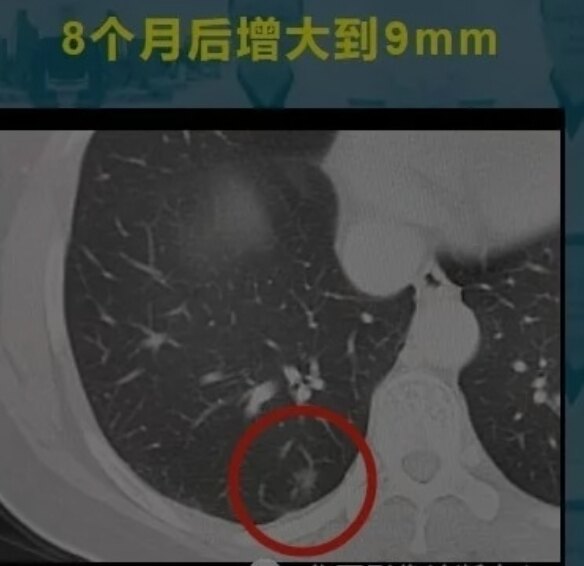

这是一位年轻女性,体检发现3mm微结节,8个月后增大为9mm的磨玻璃结节,手术病理是微浸润腺癌(MIA)。